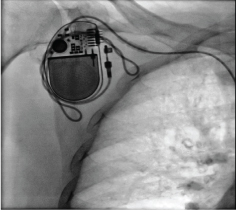

The patient was again admitted with one episode of syncope and twitching in the right upper quadrant of the abdomen. Electrocardiogram showed atrial fibrillation with a ventricular rate of 36/minute. A pulsation in her abdomen due to diaphragmatic stimulation was observed. Temporary pacemaker lead was inserted through the right femoral route and connected to the pulse generator. Fluoroscopy showed twisted ventricular lead and its retraction into the right atrium (Figure 1 and Figure 2). A diagnosis of pacemaker Twiddler's syndrome was made. Under all aseptic precautions, the pacemaker pocket was immediately reopened. The condition of the lead just after opening the pocket and after uncoiling is shown (Figure 3 and Figure 4). A new active fixation screwing ventricular lead was inserted at the right ventricular apex. The parameters were checked, R wave, the threshold, and lead impedance were 14 mV, 0.5 V, and 700 ohms, respectively. The pulse-generator was fixed on the pectoral muscle with non-absorbable suture. Postoperative hospital stay was uneventful, and the patient was asymptomatic at subsequent follow-ups..

Figure 4: The condition of the lead after uncoiling. View Figure 4